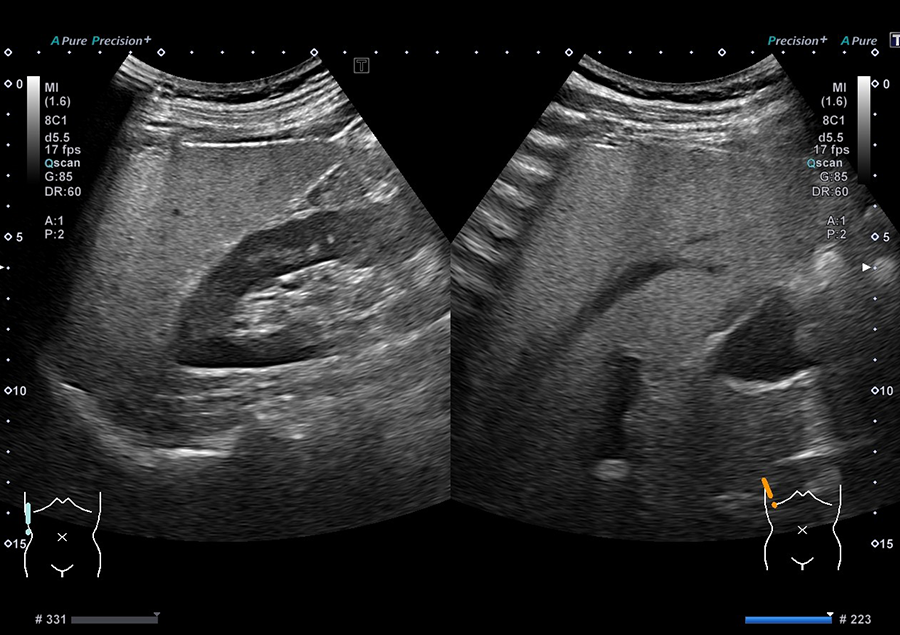

02.最新の超音波診断装置を導入

当院では、キヤノンメディカルシステムズ株式会社の超音波診断装置「Aplio a Verifia」を導入しています。

- ノイズを低減し、クリアな画質で病変を検出

- 従来の腹部エコーに比べ、広範囲を一度に撮影可能で、病変の位置がより分かりやすく確認できます

- 送信・受信技術(Advanced Sync Pulser と Advanced Beam Receiver とMulti-Harmonic Compounding)により、高精細な画像を提供

- 低流速血流の観察に適したSMI で、病変を詳細に観察

高精細な画像と優れた解析技術により、正確に観察することが可能です。

信頼性の高い検査結果を患者さまにお届けします。